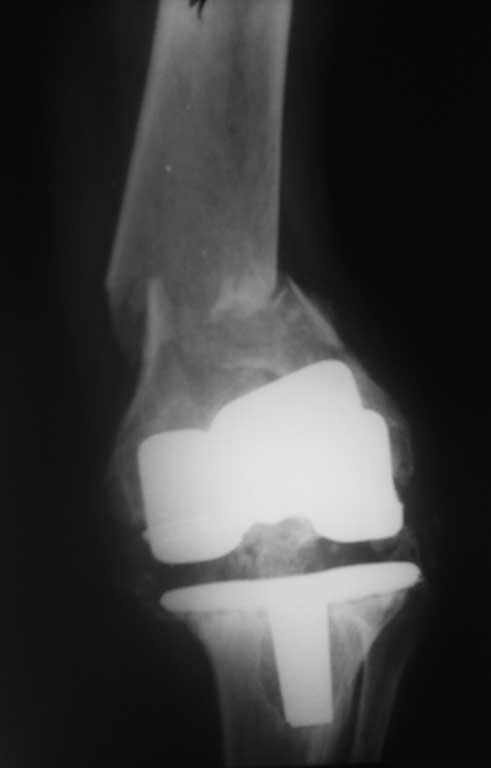

Пациентка 54 г. Два года назад выполнено протезироввние коленного сустава в одном из федеральных учереждений.

Обратилась на консультацию в связи с выраженым болевым синдромом. В тот момент находилась на лечении в терапевтичесом отделении по поводу язвенной болезни желудка. При осмотре клинико-Рлогическая картина нестабильности компонентов протеза. рекомендовано оформление инвалидности и реэндопротезирование по квотам. Через неделю пациетна упала. в результате падения переипротезный перелом на фоне нестабильного протеза. Переведена в травм.отд. наложено скелетное вытяжение. Какие варианты лечения возможны? Финансово несостоятельна.

Его (при грамотном применении) никто не отменял и на ревизию здесь ничто не повлияет. Тем более судя по снимкам имеется нестабильность тибиального компонента а про бедренный компонент не убедительно. Пока больна дождется квоты (учитывая нашу действительность) глядишь и перелом бедра срастется не вытяжении.